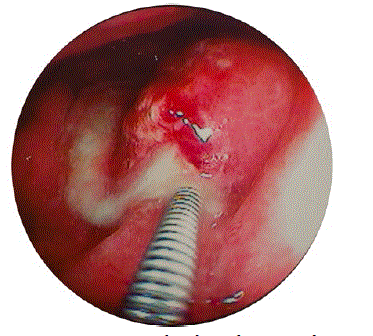

Figure 1. Intra-gastric fistula with pus exudate.